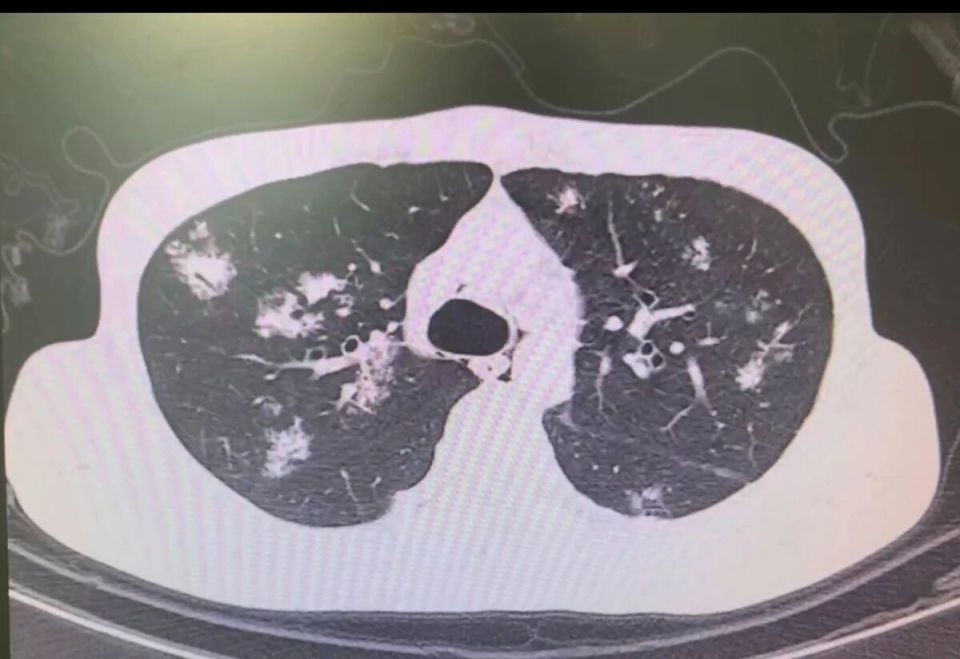

图片